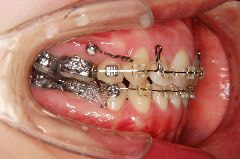

歯科矯正用アンカースクリューの使用例

例2)

➡︎